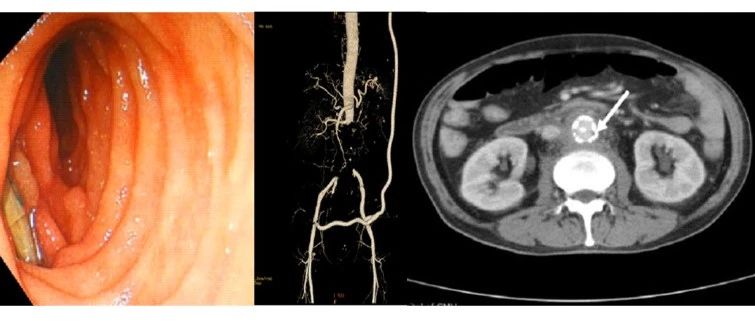

CEC 2022 I 辛世杰:腹主动脉瘤合并肠瘘的诊治